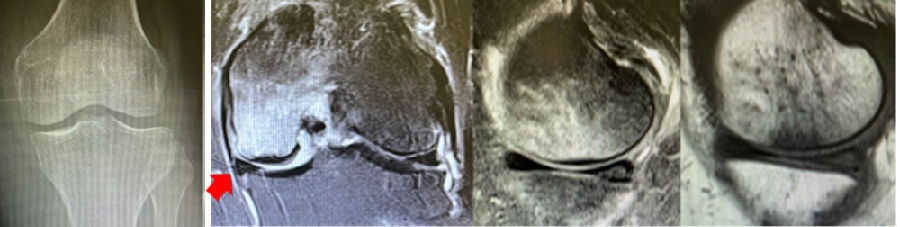

病例2:女,69岁,主诉左膝关节内侧疼痛1月余。2017年11月X光见右膝股骨髁负重区的软骨下区域出现了椭圆形透亮影,MR检查见股骨内侧髁骨坏死,合并内侧半月板外突和后角层裂,半月板相对突出百分比(RPE)25.32%,矢状位病变区域前后径为23.96mm,关节线会聚角6°。

予克氏针钻减压,消炎止痛药物口服、静滴唑来膦酸钠注射液,避免负重6周,后改部分负重至3个月,患者依从性差。2018年1月复查MR见骨髓水肿少许吸收,坏死区扩大,半月板相对突出百分比(RPE)33.53%,矢状位病变区域前后径为26.89mm,患者仍有膝关节疼痛症状,建议行手术治疗,患者拒绝手术后失访。

病例3:男,70岁,主诉右膝关节疼痛1年余。查体右膝无肿胀畸形,膝活动度0-120°,内侧间隙压痛。

已经累及44%的股骨内侧髁病变,半月板轻度突出,内侧后角水平撕裂

MRI上深度>20mm

治疗选择保守还是手术?

保守治疗4个月后复查

保守治疗后效果欠佳,坏死范围扩大、塌陷